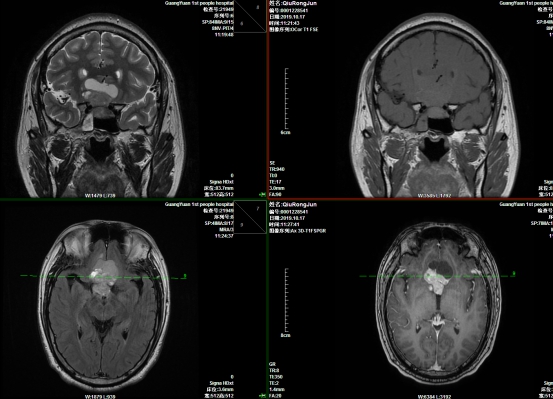

另一位手术患者邱先生,今年42岁。 3个多月前出现头痛、头昏,右眼视力下降,1个月前,头痛发作次数及持续时间明显增加,并出现四肢抽搐发作等症状。前来医院就诊,行头部MRI检查后,考虑为颅咽管瘤。由于颅咽管瘤生长位置较深,手术难度大、手术全切除率低。这个消息犹如晴天霹雳,让患者家属感到非常绝望,他们从网上了解到颅咽管瘤不仅手术切除难度大,而且术后并发症多、复发率高,如果不能治愈,很有可能将本已贫困的家庭拖垮。

颅咽管瘤切除术前

内镜下颅咽管瘤切除术术中